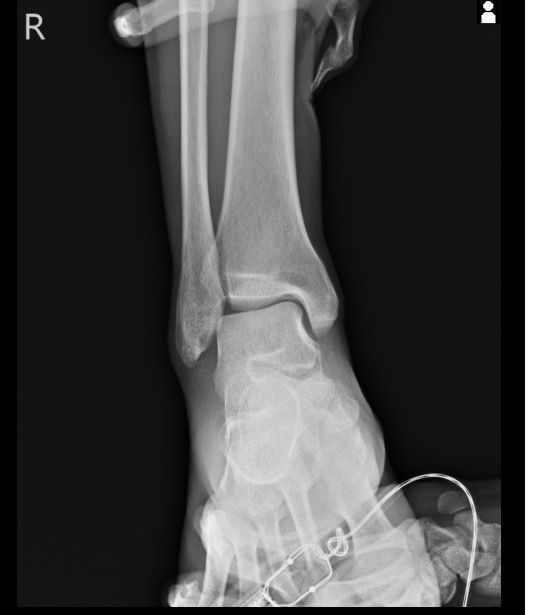

복숭아뼈 미세골절 초음파 사진 관련 질문

발목 접지른 후 치료받는 중인데요 복숭아뼈 미세골절이라고 하셨네요 3월 1일 다친뒤네 3월7일 병원방문후에 위에 초음파랑 엑스레이 촬영했고요 그뒤 반깁스 중입니다. 위에 엑스레이 상에선 안나오는데 초음파 사진에선 미세골절이 맞을까요? 골절이 경미한 수준인지 아니면 중한 건지 궁금합니다 그리고 다음주에 병원 방문 후 초음파 또 촬영하기로 했는데 그때 반깁스도 풀 수 있을까요??

미세골절 같은 경우 엑스레이서 잘 안 보일 수 있고 초음파에서 연부조직과 뼈의 상태를 좀 더 세밀하게 확인하여 확인할 수 있습니다. 미세골절이 경미한 수준이라면 초음파를 통해서 확인이 가능하며 치료 진행 상황에 따라 반깁스를 푸는 시점은 달라질수 있습니다.

미세골절은 엑스레이에서 잘 보이지 않을 수 있고 초음파에서는 연조직과 뼈의 상태를 좀 더 세밀하게 확인할 수 있습니다. 미세골절이 경미한 수준이라면 초음파에서 확인할 수 있지만 치료 진행 상황에 따라 반깁스를 풀수 있는 시점이 달라질 수 있습니다! 병원 방문 시 초음파 결과를 방탕으로 치료 계획을 조정하게 되고 전문가가 판단하는 시점에 맞춰 반깁스를 풀 수 있습니다!

발목의 복숭아뼈에 미세골절이 의심되는 경우, 엑스레이에서는 미세골절이 잘 보이지 않을 수 있습니다. 엑스레이는 큰 골절을 잘 확인하지만, 미세한 골절이나 염증 반응은 잘 나타나지 않기 때문이죠. 초음파는 조직의 변화를 보다 민감하게 감지할 수 있기 때문에, 미세골절을 발견하는 데 도움을 줄 수 있습니다. 초음파에서 미세골절이 확인되었다면, 이는 경미한 골절일 가능성이 높아요. 하지만 골절의 정확한 상태나 치유 과정을 판단하려면 정밀 검사가 필요하죠

미세골절의 치료는 시간이 필요하며, 반깁스를 착용하는 이유는 발목에 가해지는 부담을 줄이고, 골절 부위의 안정화를 돕기 위함입니다. 다음 병원 방문 시 초음파 촬영을 통해 골절의 치유 상태를 확인한 후, 의사가 반깁스를 풀어도 될지 결정할 듯 해요. 만약 골절이 잘 치유되었고 통증이 없다면 반깁스를 풀고 재활 운동을 시작할 수 있을 거구요. 하지만 치유가 더 필요한 경우에는 여전히 반깁스를 착용하거나 다른 치료 방법이 필요할 수 있겠죠